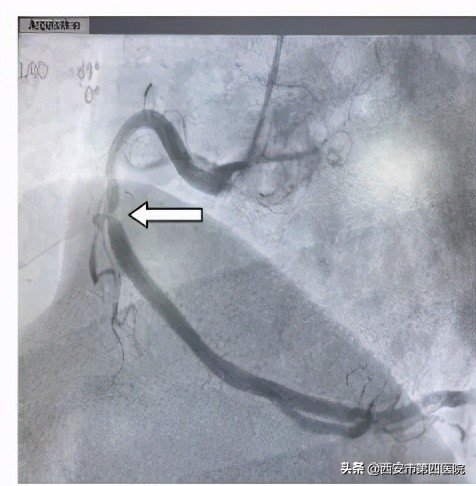

陈某术前-右冠重度狭窄

为了更精准了解管腔病变情况,经过由中国科学院科技服务网络计划重点项目自主研发的OCT检查后,发现刘某前降支中段狭窄处斑块负荷严重,斑块薄层纤维帽,存在脂质池,有随时发生破裂可能,管腔面积最小处仅为1.07mm2,提示血管严重狭窄。陈某右冠中段存在破裂斑块,与家属商议后,决定给予支架干预治疗。

陈某右冠术后